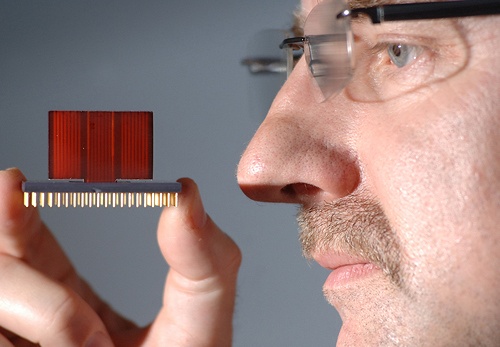

Сегодня компанией GenePeeks была представлена технология Matchright, которая позволяет создавать цифровые эмбрионы после смешивания ДНК двух людей, собирающихся стать родителями.

С помощью нее можно составить чёткое представление о здоровье будущего ребёнка этих людей, а также узнать о его цвет глаз, примерный рост и вес и т.д.

Обычно скрининг генетических нарушений включает в себя расшифровку ДНК будущих родителей. Matchright, используя эту информацию для воссоздания в цифровом виде процесса генетической рекомбинации, позволяет медикам взглянуть на набор генов возможных эмбрионов.

До того, как женщина выберет донора спермы, алгоритм GenePeeks представит тысячу гипотетических комбинаций для каждого претендента. Matchright позволяет обнаруживать мутации в отдельных генах, способные вызвать порядка 500 редких заболеваний. Заплатив около $2000 за данную услугу, женщине предоставят список потенциально безопасных доноров.

Для проверки данного метода использовали информацию неизвестных мужчины и женщины, чьи геномы были упорядочены в рамках проекта 1000 Genomes.